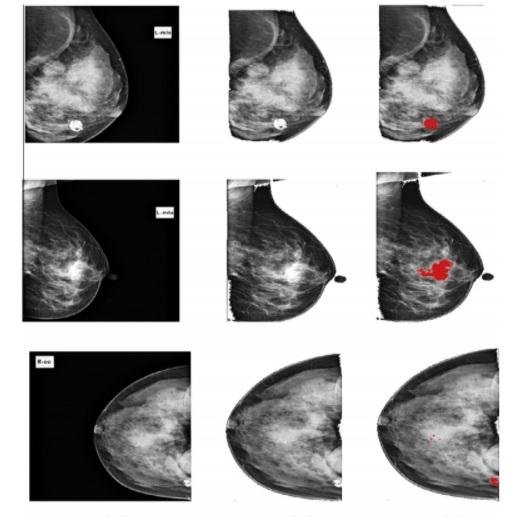

Breast cancer is the second leading cause of cancer death in women. Accurate early detection can effectively reduce the mortality rate caused by breast cancer. Masses and microcalcification clusters are an important early signs of breast cancer. However, it is often difficult to distinguish abnormalities from normal breast tissues because of their subtle appearance and ambiguous margins. Computer aided diagnosis (CAD) helps the radiologist in detecting the abnormalities in an efficient way. This paper investigates a new classification approach for detection of breast abnormalities in digital mammograms using Particle Swarm Optimized Wavelet Neural Network (PSOWNN). The proposed abnormality detection algorithm is based on extracting Laws Texture Energy Measures from the mammograms and classifying the suspicious regions by applying a pattern classifier. The method is applied to real clinical database of 216 mammograms collected from mammogram screening centers. The detection performance of the CAD system is analyzed using Receiver Operating Characteristic (ROC) curve. This curve indicates the trade-offs between sensitivity and specificity that is available from a diagnostic system, and thus describes the inherent discrimination capacity of the proposed system. The result shows that the area under the ROC curve of the proposed algorithm is 0.96853 with a sensitivity 94.167% of and specificity of 92.105%.